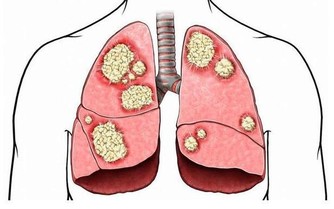

當身體中的濕氣過重時,人就會感覺到全身都不舒服,不是覺得這裡痛,就是那裡酸,沒有辦法專心去做一件事情,會嚴重影響到我們的生活與學習。而且,當身體的濕氣累積到一定程度的時候,身體就會產生各種各樣的毛病。而夏天又是一個濕氣增長的季節,因此,今天我們就來跟大家談一談怎樣趕走我們身體內部的濕氣。